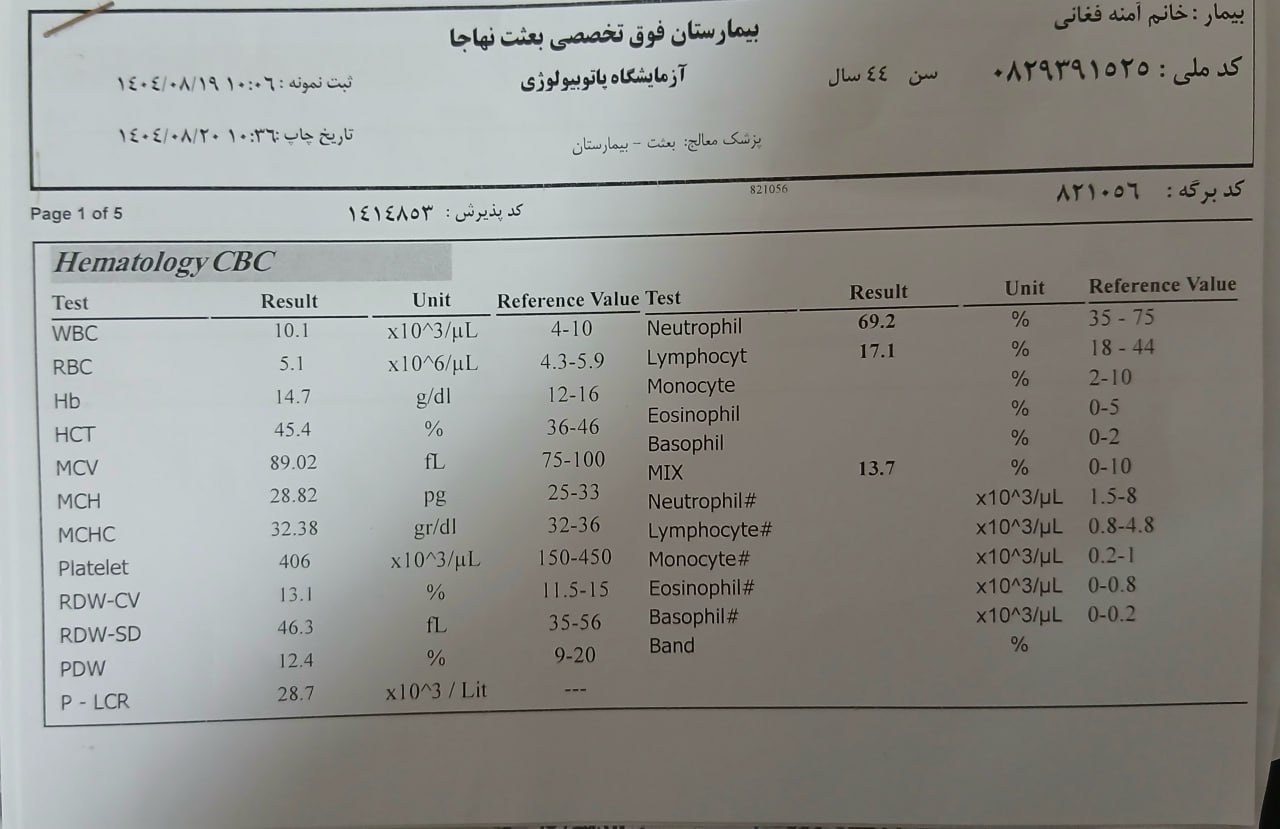

به ترتیب؛ روز ها: ۱۹ آبان, ۲۸ آذر, ۲۹ آذر, ۳۰ آذر

به ترتیب؛ روز ها: ۱۹ آبان, ۲۸ آذر, ۲۹ آذر, ۳۰ آذر

۱۹ آذر

۱۹ آذر